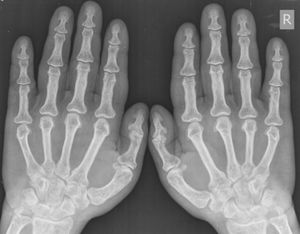

A 7-year-old male presented with pain after falling on an outstretched hand.